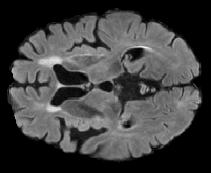

In order to analyze qualitatively the results of our generator, we extract slices with different WMHs loads, Table 4 shows the reconstruction results for three different levels of loads. As we can see in the first row, both methods produce a similar response in regions with a low load of lesions, it can be observed that generated images are similar to the real FLAIR images in the left, and these not present evident structural distortions. However, it can be noted images exhibit blurred effects, which can be due to L2 based optimization, more complex generative networks with adversarial loss optimization as GANs tend to eliminate blurred effect but at the expense to produce structural distortions. In the application presented in this work it is important to preserve the structural information, thus, our L2 based optimization present a good balance between preserve structural information and blurred effects. In the second and third column, it can be observed the performance of both methods when facing the presence of lesions, as can be seen, both methods have a good response to large and contiguous lesions. It also can be noted both methods tend to produce poor performance in small and diffuse WMHs marked in red, note, these lesion do not exhibit identifiable patterns in T1 images, however it can be seen that our proposed method is more sensitive to these patterns which enable to highlight some small regions as those marked in green.

FLAIR T1 Offline synthesis Proposal

Table 4: Results of Generation for all the proposed methods,